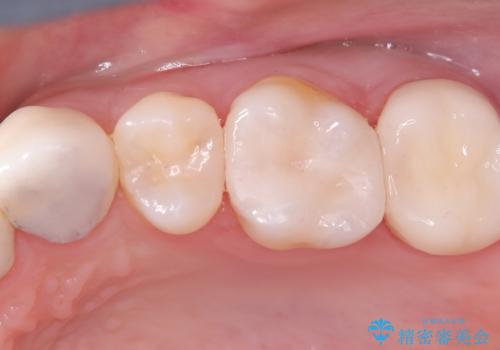

- 虫歯の治療を希望されました。一番奥の歯は虫歯が深かったことから神経を部分的に残す治療法(生活歯髄療法)や神経の治療(根管治療)についても説明し、治療介入をしました。

材料の特性を説明し、材質はどちらもセラミック、手前の歯は部分的な詰め物、奥の歯は被せ物での修復となりました。

左上7番は治療前の神経の検査では正常の範囲内の値を示しました。虫歯を削っていったところ神経まで到達したため、神経を部分的に残す治療法を選択しました。その後痛み等症状が出ず、また、神経の反応も正常であったため、被せ物にしています。